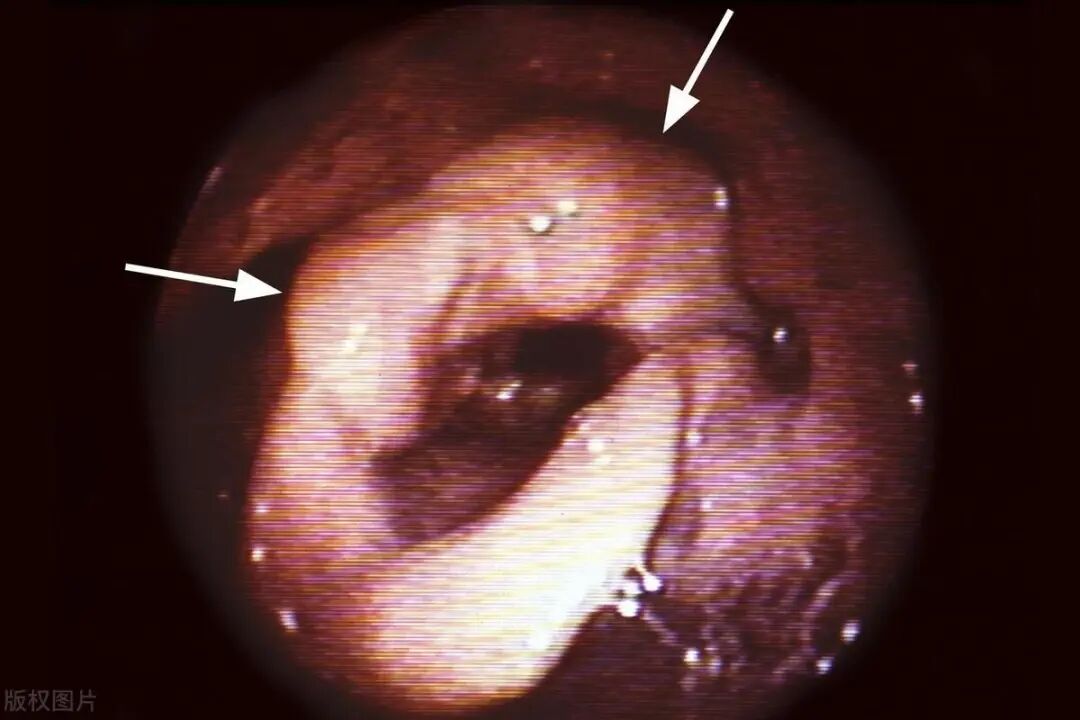

01喉镜检查

喉镜检查是发现早期喉癌的主要手段之一。医生使用喉镜直接观察喉部情况,包括声带、喉咙等区域的异常变化,以及是否存在肿瘤、溃疡等病变。